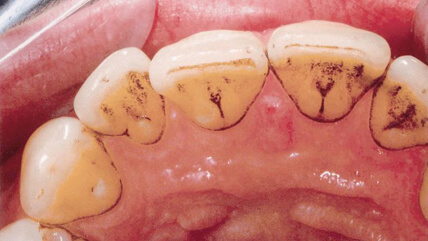

STEP.4 / エアフロー

バイオフィルム、ステイン(着色汚れ)、早期歯石を除去

エアフローを使ってバイオフィルム、ステイン(着色汚れ)、早期歯石を天然歯、補綴物、インプラント周囲から除去します。エアフローで使用するパウダーは粒子の直径がわずか14μmですので、細かい汚れを吸着させると同時にジェット水流で洗い流します。染め出しをすることで、バイオフィルムを見落とさずに完全に除去出来ます。

コーヒーや紅茶、タバコのヤニなどの着色汚れが落ち、本来の白い歯と輝きが戻って表面がツルツルになります。1回でかなりきれいになります。

- エアフローによる治療前

- 歯と歯の間のむし歯が歯の汚れによって、歯面清掃を行う前には見えにくくなっています。

- エアフローでの治療後

- 歯と歯の間のむし歯がわかるようになりました。このように、口腔内の問題が見過ごされるのを防ぐことが出来ます。